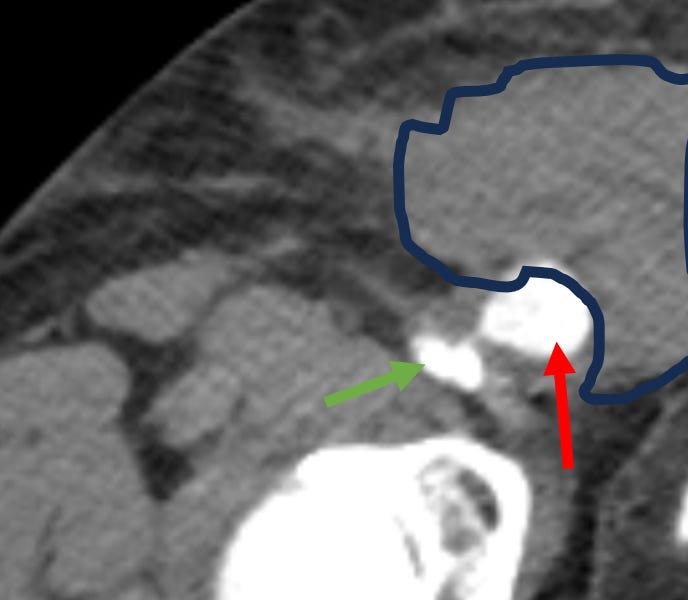

You get the CTA which shows concern for an actively leaking pseudoaneurysm. The red arrow shows the aneurysm, the green arrow shows the femoral artery, and the blue freeform outline shows the hematoma around the aneurysm, which extended posteriorly, up Mrs. Chadwick’s flank.